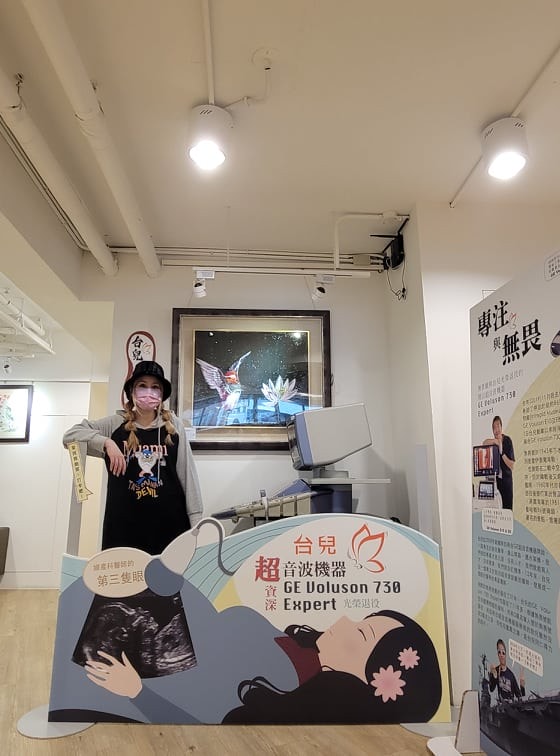

首先這是七樓報到的地方

診所其實沒有很富麗堂皇

給人一種很樸實的感覺XD

不過總之這空間挺寬敞

硬要來拍一下打卡照!